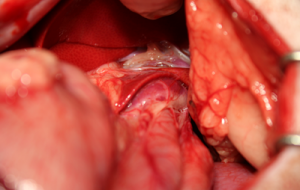

実際のシャント血管です。

シャント血管を確認後、絹糸にて仮遮断し、門脈圧の過剰な上昇がないことを門脈圧測定にて確認後、完全結紮を行いました。